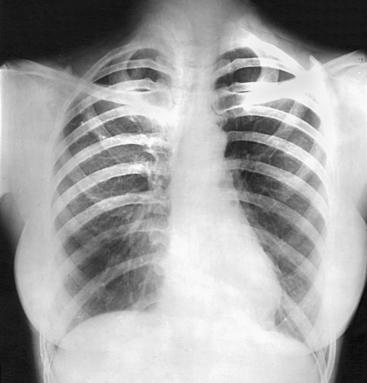

For radiography of the heart and lungs, the patient is placed in an upright position whenever possible to prevent engorgement of the pulmonary vessels and to allow gravity to depress the diaphragm. Of equal importance, the upright position shows air and fluid levels. In the recumbent position, gravitational force causes the abdominal viscera and diaphragm to move superiorly; it compresses the thoracic viscera, which prevents full expansion of the lungs. Although the difference in diaphragm movement is not great in hyposthenic individuals, it is marked in hypersthenic individuals. Figs. 10-10 and 10-11 illustrate the effect of body position in the same patient. The left lateral chest position (Fig. 10-12) is most commonly employed because it places the heart closer to the IR, resulting in a less magnified heart image. Left and right lateral chest images are compared in Figs. 10-12 and 10-13.

Respiration: Full inspiration. The exposure is made after the second full inspiration to ensure maximum expansion of the lungs. The lungs expand transversely, anteroposteriorly, and vertically, with vertical being the greatest dimension.